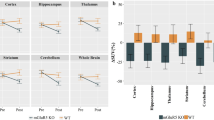

Mean time–activity curves (TAC) are presented in Fig. 2. After intravenous bolus injection of [18F]FPEB, a rapid uptake was observed in the 5 ROI examined (i.e., the caudate/putamen, amygdala, thalamus, cingulate, and cerebellum). After a peak (10 min post-injection), we observed that the maximum [18F]FPEB binding was on the striatum. Then it decreased slowly and linearly until the end of the acquisition. On the contrary, in the cerebellum, the uptake decreased sharply and remained low and stable from 20 min post-injection (p.i.). Figure 3A illustrates the averaged [18F]FPEB SUV calculated from the TAC for the different ROI and Fig. 3B illustrates microPET images of SUV as an overlay on a MRI template.

A [18F]FPEB SUV (mean ± SD) after test–retest and NAc challenge in six relevant regions of interest. B Illustrations of averaged [18F]FPEB SUV images after test and NAc challenge and VOI templates (PMOD) overlaid with [18F]FPEB template. C SUVr calculated with the cerebellum as the reference region and absolute ΔSUVR for test, retest, and NAc challenge in [18F]FPEB small animal PET (n = 9).

For both challenge conditions (test, retest, and NAc), we calculated the SUVr (SUV ratio to cerebellum) in five relevant brain areas (caudate putamen, amygdala, thalamus, cingulate, and frontal cortex) on small-animal PET as well as the absolute percentage changes across the baseline and NAc condition (Fig. 3C). SUVr values from test and retest (n = 9) were not significantly different in any region (p > 0.05). Similarly, Friedman two way analysis did not show any significant difference between SUVr values from baseline and from NAc challenge in any regions of interest (p > 0.05).